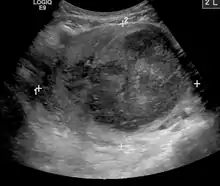

- Kidney cancer: kidney tumors such as renal cell carcinoma can be treated with image-guided ablation (RFA, MWA, cryotherapy) with similar results to partial nephrectomy. Generally, surgery via an either partial or total nephrectomy (removal of kidney) is most often curative but for patients with a smaller lesion or who are not ideal surgical candidates, radiofrequency or cryoablation ablation can be a curative option.[70] Advantages of cryoablation include the ability to visualize the ice ball as well as use more than one probe simultaneously to create the desired ice ball shape. Benign kidney tumors such as angiomyolipomas can be treated with transarterial embolization to shrink the tumor size and reduce the risk of rupture/bleeding. Other embolizations are also performed for symptom relief or prior to surgery to reduce bleeding.[71]